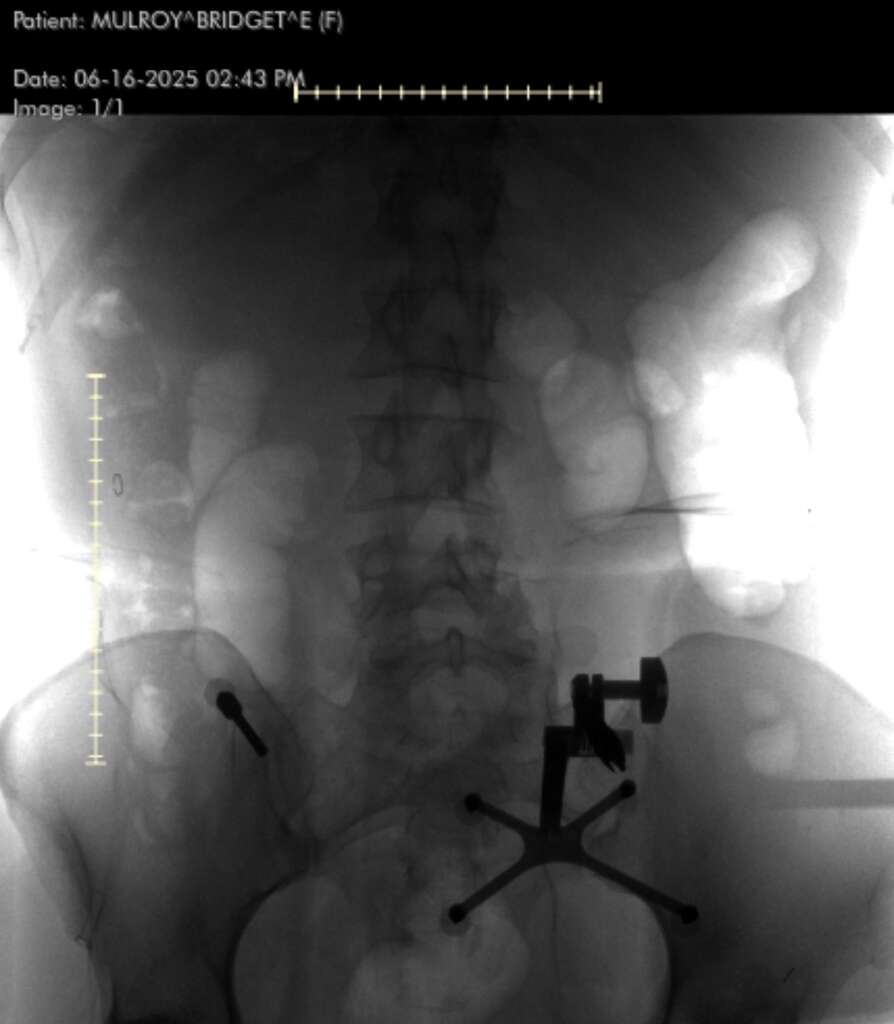

He performed a minimally invasive posterior lumbar instrumentation from L2 to L5. That means he made small incisions guided by real-time navigation using a machine called the O-arm—a rotating intraoperative CT scanner. A localizing pin in my pelvis communicated with a computer, which told him exactly where to place each screw.

“Once the screws are inserted,” he explained, “I use an X-ray to place the rods. The key decisions involve knowing which levels to include, ensuring screw trajectory is perfect, and having a plan if something doesn’t go right.”

Instead of using an external brace, Dr. Lopez used hardware—screws and rods—to create internal support.

“Technically, you didn’t have a spinal fusion,” he clarified. “You had spinal instrumentation and stabilization. A fusion requires bone grafts and biologic processes to encourage new bone growth.”